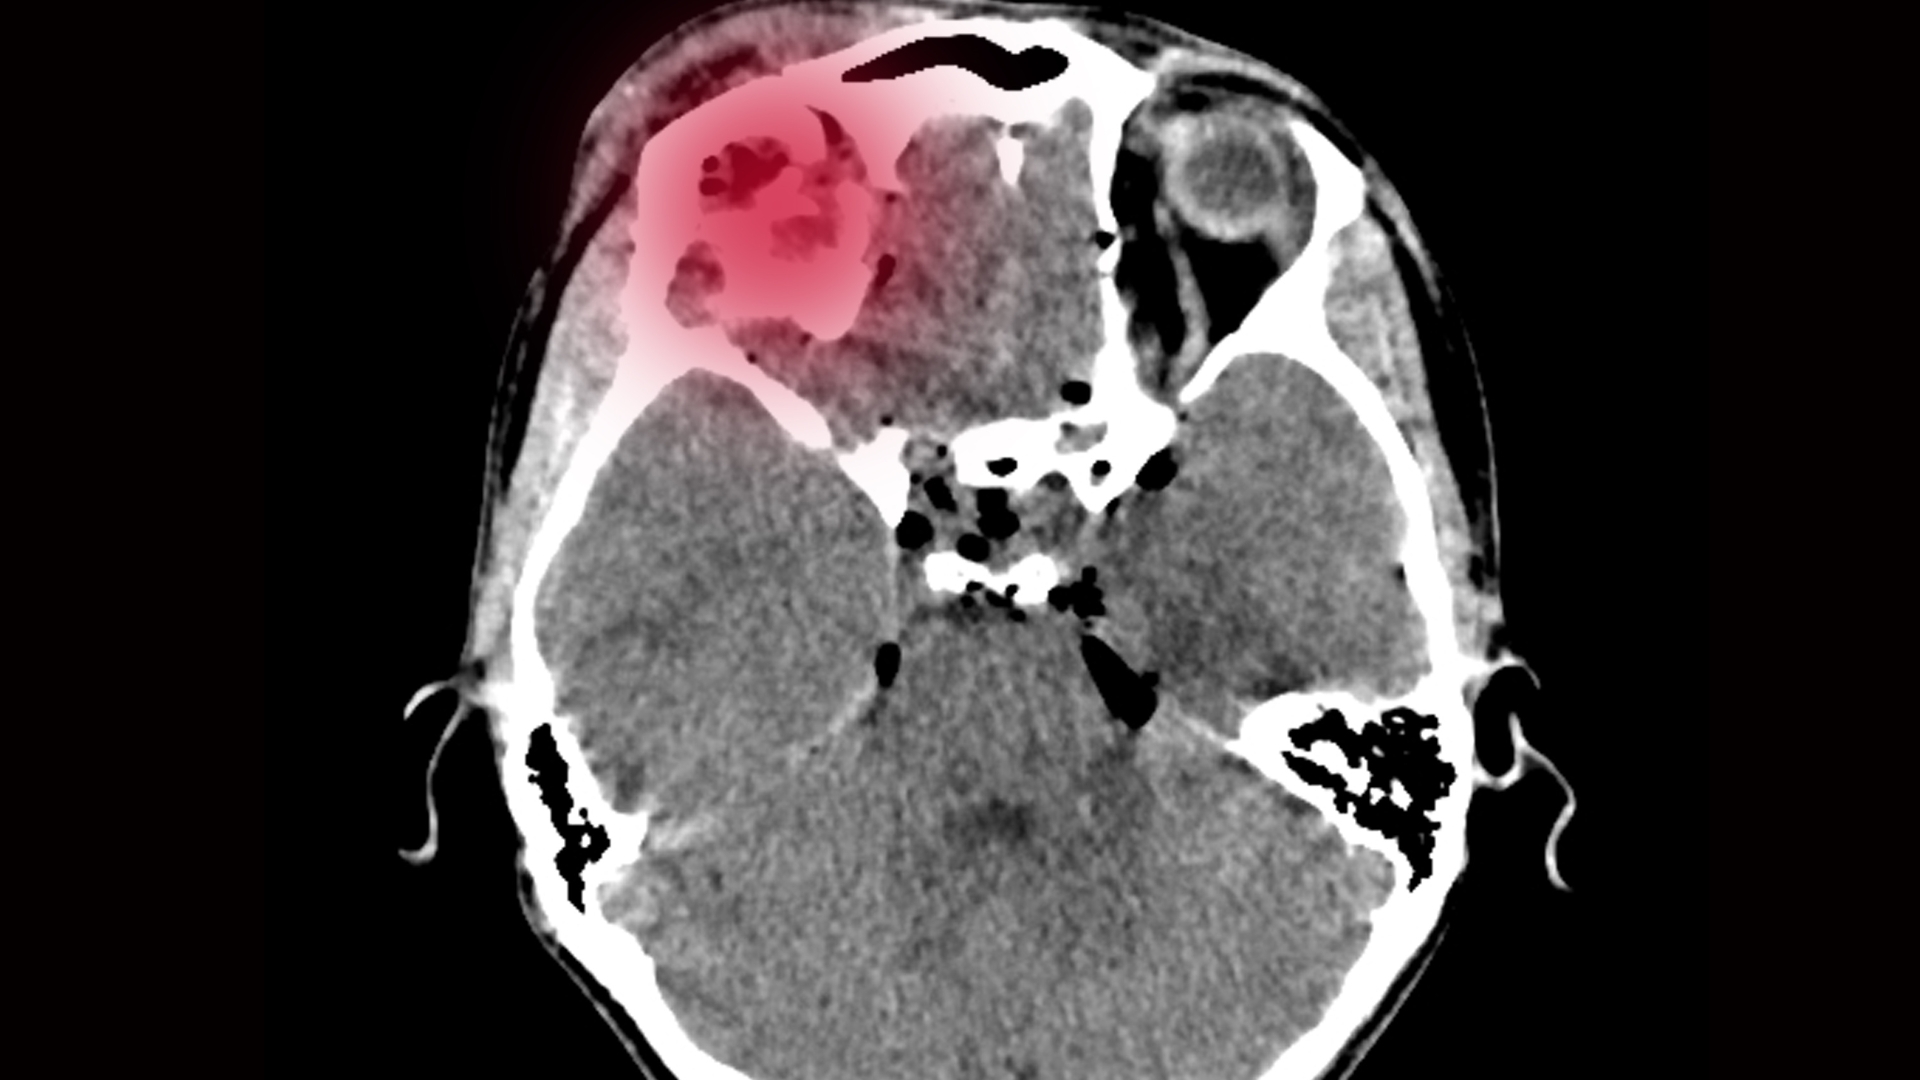

Chụp X-quang não có ưu điểm trong việc đánh giá cấu trúc xương sọ, nhưng không phải là phương pháp toàn diện để khảo sát não bộ. Kỹ thuật này không cho thấy được nhu mô não, mạch máu não hay các tổn thương bên trong hộp sọ.

Do đó, phim X-quang không phát hiện được các tình trạng như máu tụ nội sọ, phù não hoặc tổn thương vi thể của mô não. Điều này đồng nghĩa với việc một người vẫn có thể bị chấn thương sọ não dù hình ảnh X-quang không ghi nhận bất thường ở xương. Vì vậy, kết quả chụp luôn cần được đánh giá cùng với triệu chứng lâm sàng và thăm khám thực tế.

Nghi ngờ xuất huyết nội sọ hoặc tụ máu ngoài màng cứng.

Trong những tình huống này, chụp CT sọ não thường được ưu tiên vì cho hình ảnh cắt lớp chi tiết, giúp phát hiện nhanh máu tụ và tổn thương nhu mô não trong giai đoạn cấp cứu. MRI có thể được chỉ định khi cần đánh giá kỹ hơn cấu trúc mô mềm, dây thần kinh hoặc các tổn thương mạn tính chưa rõ nguyên nhân.